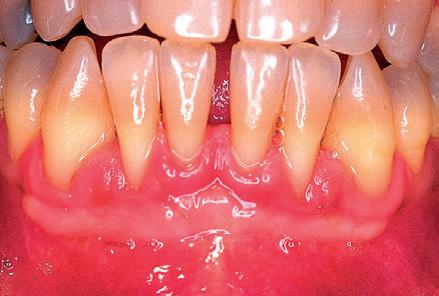

Para interpretar adecuadamente este caso, debemos situarnos de nuevo en la década de los noventa. Mujer de 19 años que desarrolló recesiones gingivales durante el transcurso del tratamiento ortodóntico. Llama la atención la

Fig 9: Año 1997. Mujer de 19 años que presenta recesiones gingivales en 31-41. Se aprecia un biotipo extremadamente no y ausencia de profundidad vestibular.

presencia de un biotipo extremadamente no y una ausencia de profundidad vestibular. (Fig. 9) Se realizó un autoinjerto libre epitelizado a nivel del 31 y 41 con el que se cubrió totalmente la super cie radicular expuesta. Se creó una dimensión volumétrica de encía insertada adecuada y se profundizó el vestíbulo (Fig. nº 10). A diferencia del primer caso, el injerto cubrió desde el primer momento la totalidad de la super cie radicular, por lo que no fue necesario que se desarrollara la inserción reptante.

A partir de ahora, vamos a focalizar la atención en el diente 42. Su encía es na y transparente. El injerto no abarcó esta zona debido a las características de la bromucosa palatina. La paciente se marchó a vivir a Escandinavia y acudió de nuevo a nuestra consulta nueve años después. ¿Qué había ocurrido durante este periodo de tiempo? Nada sorprendente hasta el momento. Había ocurrido lo que tenía que ocurrir, es decir, el desarrollo de una recesión a nivel del 42 y la excelente estabilidad del autoinjerto libre epitelizado del 31-41 (Fig. nº 11). Sin embargo, lo realmente sorprendente tiene lugar 19 años después de haberse practicado el injerto, es decir, diez años después de la imagen que se muestra en la Fig. 11. La encía insertada localizada en 31 y 41, se desplaza lateralmente hacia el diente 42 (Fig. nº 12) dotando a este diente de una adecuada cantidad de encía insertada. Es como si se hubiera producido un ALE pro láctico de manera espontánea a nivel del 42, lo que implica un stop en el avance de la recesión de este diente.

Fig 10: Resultado a los 2 años. Se ha cubierto completamente la super cie radicular expuesta y se ha creado una adecuada cantidad de tejido queratinizado. En este caso, no se produjo el fenómeno de inserción reptante, ya que el injerto cubrió desde el primer momento, la totalidad de la super cie radicular. Sin embargo, hay que prestar atención a la encía del 42, que es extremadamente na.

Fig 11: Resultado a los 9 años. El injerto se mantiene estable, pero se ha desarrollado una recesión a nivel del 42. Fig 12: Resultado a los 19 años. Compárese la diferencia con la Fig 11. Curiosamente, el injerto se ha extendido, de manera espontánea hacia el 42, dotándole a éste de una adecuada cantidad de encía insertada. ¿Por qué ha tardado tantos años el injerto en desarrollar este fenómeno?